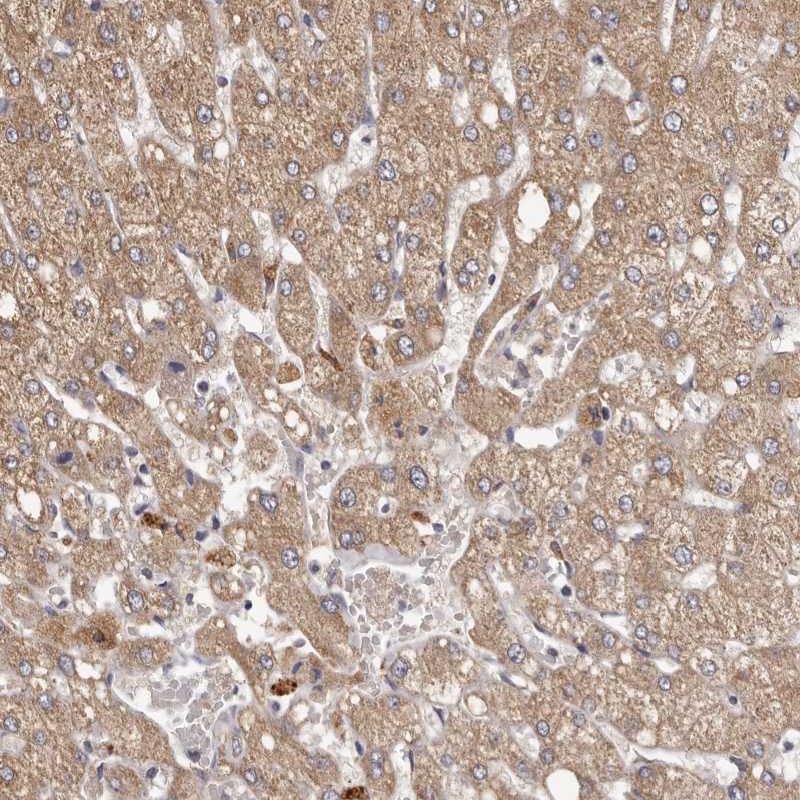

Immunohistochemical staining of human liver shows moderate cytoplasmic positivity in hepatocytes.